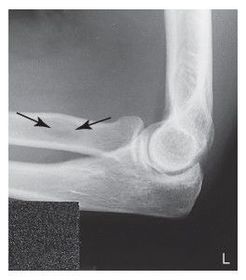

C. anterior fat pad D. posterior fat pad E. supinator fat stripe (not visible)

Which fat pad of the elbow will only appear on x-ray if there's a joint pathologic process? Posterior Fat Pad

Why does the elbow need to be in 90 degree flexion to determine whether the posterior fat pad is visible or not? When elbow is flexed more or less than 90 degrees it pushes the fat pad into different position, it can show up on x-ray then when there's no pathologic issue